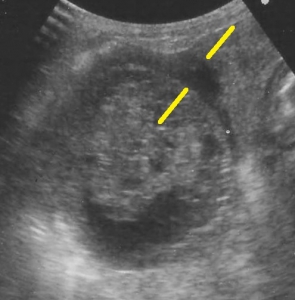

下の超音波像は胆嚢破裂の初期の胆嚢をみたものです。中央部に胆嚢粘液嚢腫がみられますが、黄色腺の間に示されている「三角形の黒いエリア」が胆嚢壁の外側に広がっています。これは胆嚢壁の裂け目から内部の「粘液状物」が腹腔内に出ていたり、周囲の組織との強い癒着や炎症を示す画像です。ご参考までに右が正常の胆嚢です。